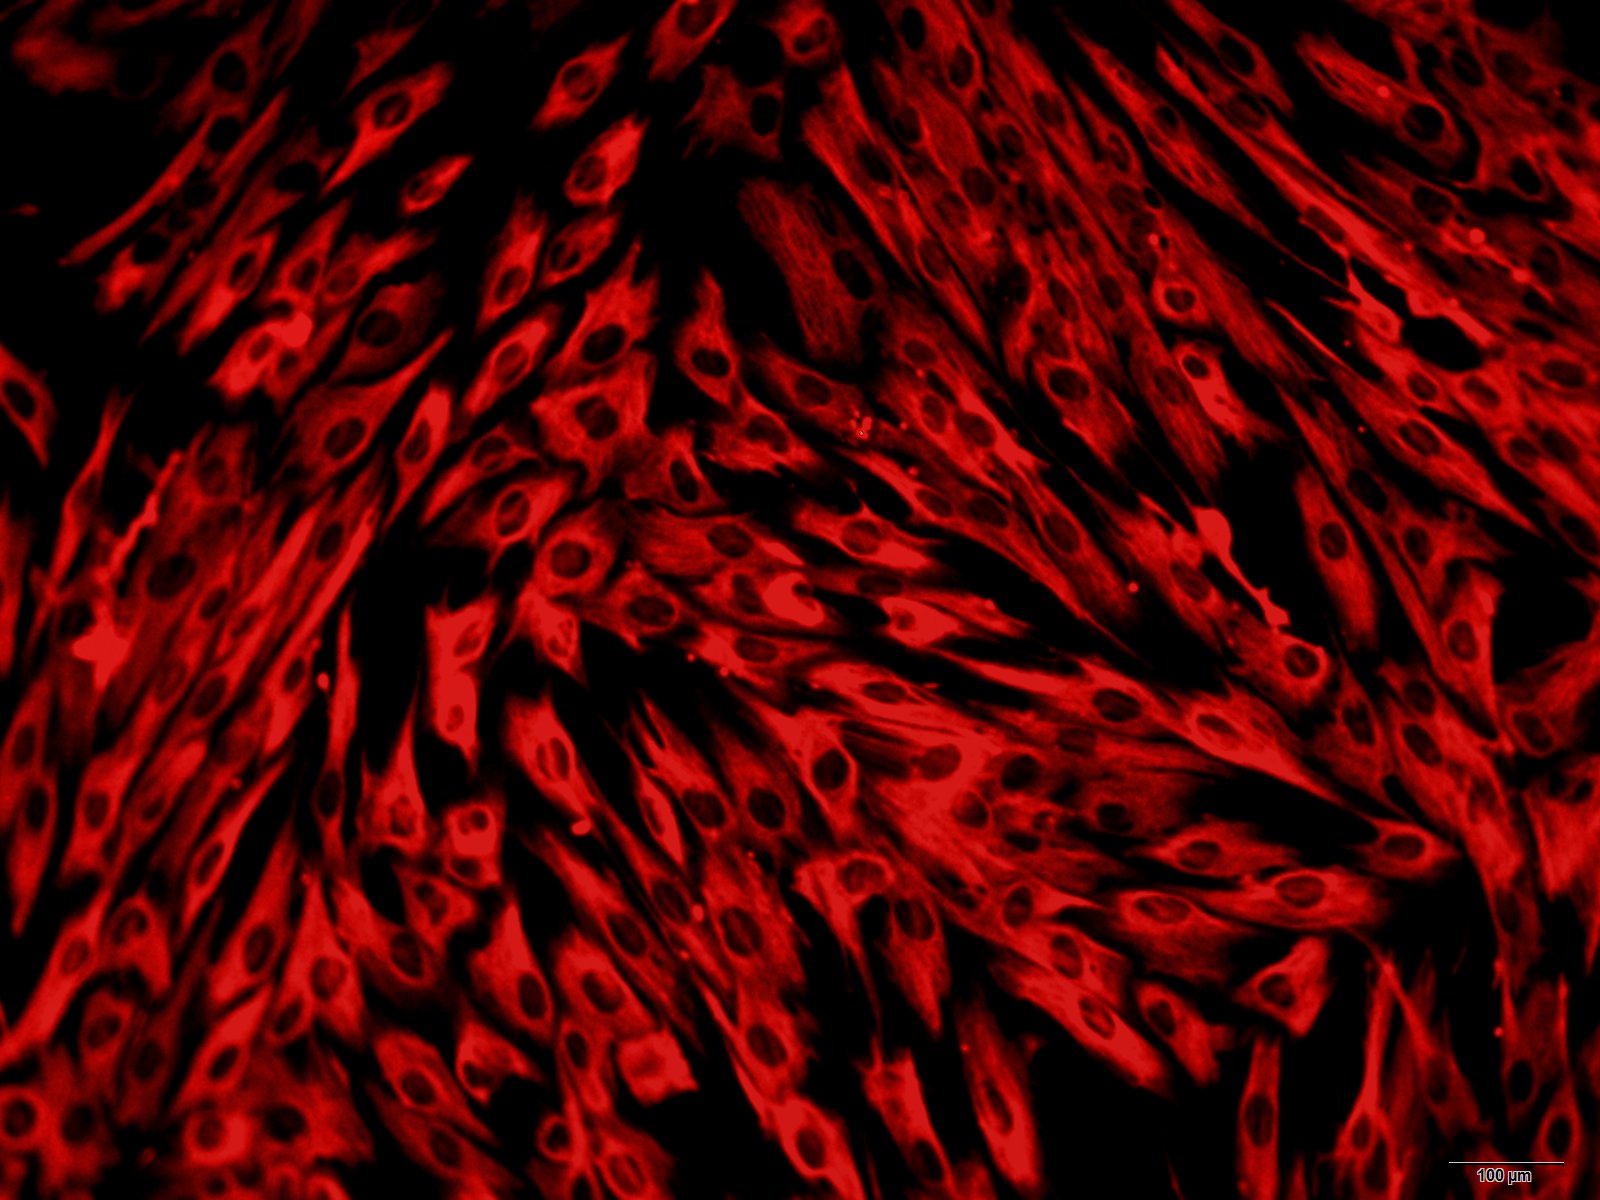

本公司生产的人小肠平滑肌细胞采用酶解法制备而来,细胞总量约为5×105/T25方瓶,α-SMA、Desmin呈阳性,细胞纯度可达90%以上,且不含有HIV-1、 HBV、HCV、支原体、细菌、酵母和真菌等。

人小肠平滑肌细胞分离自人小肠组织。小肠位于腹中,上端接幽门与胃相通,下端通过阑门与大肠相连,是食物消化吸收的主要场所。小肠有三种功能即消化、吸收和分泌及运动功能,其中以吸收和分泌功能为主。平滑肌细胞的收缩是负责肠蠕动的动力,促使食物向下运动。